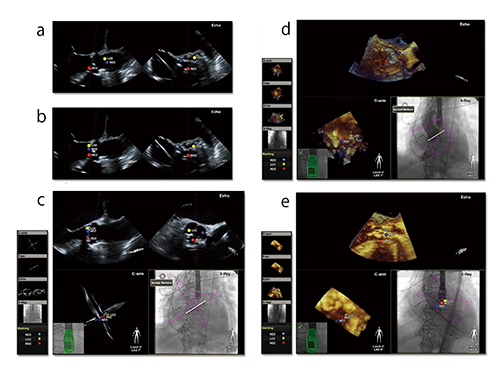

■EchoNavigator

2013年に発表した新機能“EchoNavigator”は,Live 3D TEE ImageとX線透視画像をフュージョンすることを可能とした。透視撮影を開始した瞬間に経食道プローブヘッドの向きを認識し,フュージョン画像(Live 3D TEE Image+X線透視画像)がリアルタイムにモニタに表示される。このフュージョン画像は,常に透視装置のCアームの動きと連動し,リアルタイムに同じ角度で同期して表示される。このことにより,経食道心エコー術者とカテーテル術者が,まったく同じモニタを通して見ることが可能となり,それぞれの術者が非常に多くの情報を同時かつシンプルに評価できるので,直感的でスムーズな手技を可能とし,より安全で精度の高い治療を行えるようになる(図2)。

図2 EchoNavigator表示画面

(Live 3D TEE ImageとX線透視画像のフュージョン)

また,EchoNavigatorでは,Live 3D TEE ImageやTEE 2D Imageから得られた弁や心房中隔欠損孔などの画像に,解剖学的位置情報(以下,マーカー)と呼ばれるターゲットを置くことが可能になった。このマーカーは,リアルタイム透視画像にもリンクし位置情報として表示される。術者の主観的な判断のみでなく,エコー情報から得たリアルタイムの位置情報を確認でき,これによってより安全かつ適切なカテーテルによるデバイスのポジショニングが可能となる。

透視画像はその特性上,軟部組織の描出が難しい。それに対しLive 3D TEE Imageは,弁や軟部組織の把握や時間分解能で圧倒的に優れている。Live 3D TEE Imageからの位置情報を,マーカーを介してX線透視画像に表示できるメリットは,特に評価が難しい軟部組織などへの位置やアプローチのガイドを,X線透視画像から確認できることである。特に,今後認可が下りるさまざまなデバイスを留置する手技では,必要不可欠な技術となると考える(図3)。

これからますますSHDに対する経皮的カテーテル治療が増えるのは事実であるが,EchoNavigatorにより,精度と安全性が共に向上する。Live 3D TEE ImageとX線透視画像をリアルタイムにフュージョンできるEchoNavigatorの登場は,画期的な機能と言えるであろう。

図3 EchoNavigatorによるX線透視画像へのマーカー表示